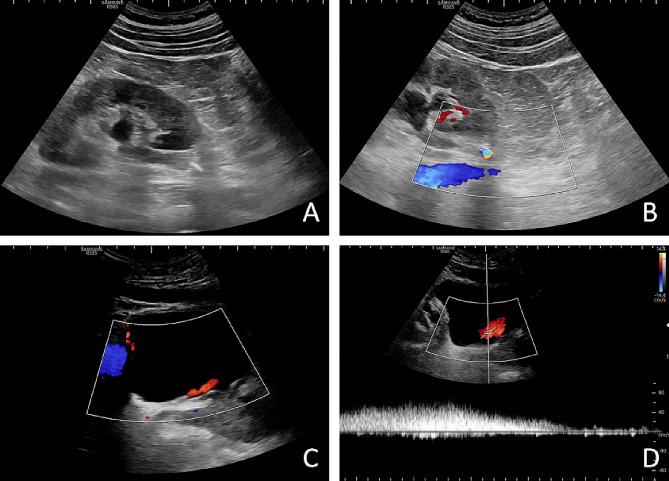

Clinical and ultrasound data were collected consecutively from patients receiving conservative treatment for ureteral stones, and the outcome of spontaneous passage was followed up for 1 month. Ultrasound variables independently associated with the risk of spontaneous stone passage were screened. A logistic regression prediction model was constructed based on the independent risk factors, and the discriminative efficacy and clinical utility of the prediction model in inferring the risk of spontaneous passing were assessed by the receiver operating characteristic (ROC) curve, calibration curve and clinical decision curve.

A total of 163 patients undergoing conservative treatment for ureteral stones were included in the study, with a mean age of 45.95 ± 13.01 years. Among them, 47 cases (28.83%) experienced failure of spontaneous stone passage. Multivariable analysis revealed that stone length (OR: 2.622, P = 0.027), distal stone location (OR: 0.219, P = 0.003), and ureteral jetting frequency (OR: 6.541, P < 0.001) were independent risk factors for spontaneous stone passage. A prediction model incorporating stone length, stone location, and affected ureteral jetting frequency was developed to assess the risk of spontaneous stone passage. The area under the ROC curve was 0.814 (95% CI: 0.747-0.882), indicating good discriminatory power. The prediction model also demonstrated favorable net clinical benefit.

A prediction model based on ultrasound-derived stone length, location, and ureteral jetting frequency can accurately evaluate the risk of spontaneous stone passage in patients with ureteral stones, providing a basis for optimizing the clinical decision-making on ureteral stones, and has reliable clinical application value.